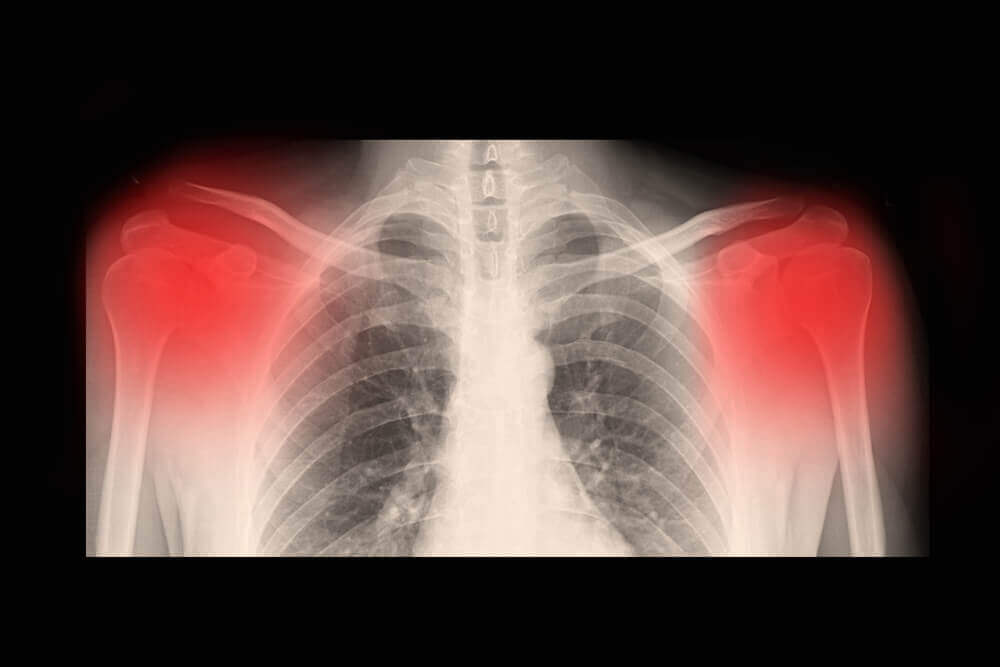

Le diagnostic est généralement fait après une révision clinique. Habituellement, cela est complété par des rayons X, CT et/ou IRM. De même, une échographie à haute résolution peut être indiquée pour évaluer le niveau d’évolution de l’arthrose.